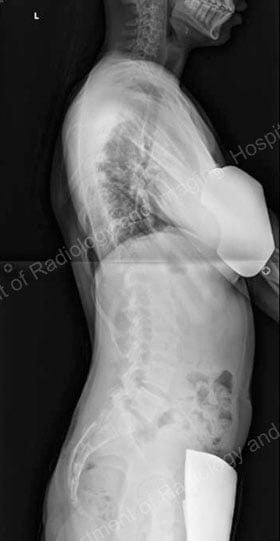

To assess the curve further, X-ray images or low-dose radiation EOS images are taken from the front and side views [Figures 4, 5]. Side-bending X-rays may also be taken to assess the flexibility of the curve or curves. Sometimes these images reveal two curves: the first curve to appear in the spine (the primary curve) and the compensatory curve that the patient develops through his or her effort to maintain an erect posture.

Figures 4 (left) & 5 (right): Anterior to posterior (front to back) and lateral

(side) X-rays showing a scoliosis curve from the back and side, respectively.